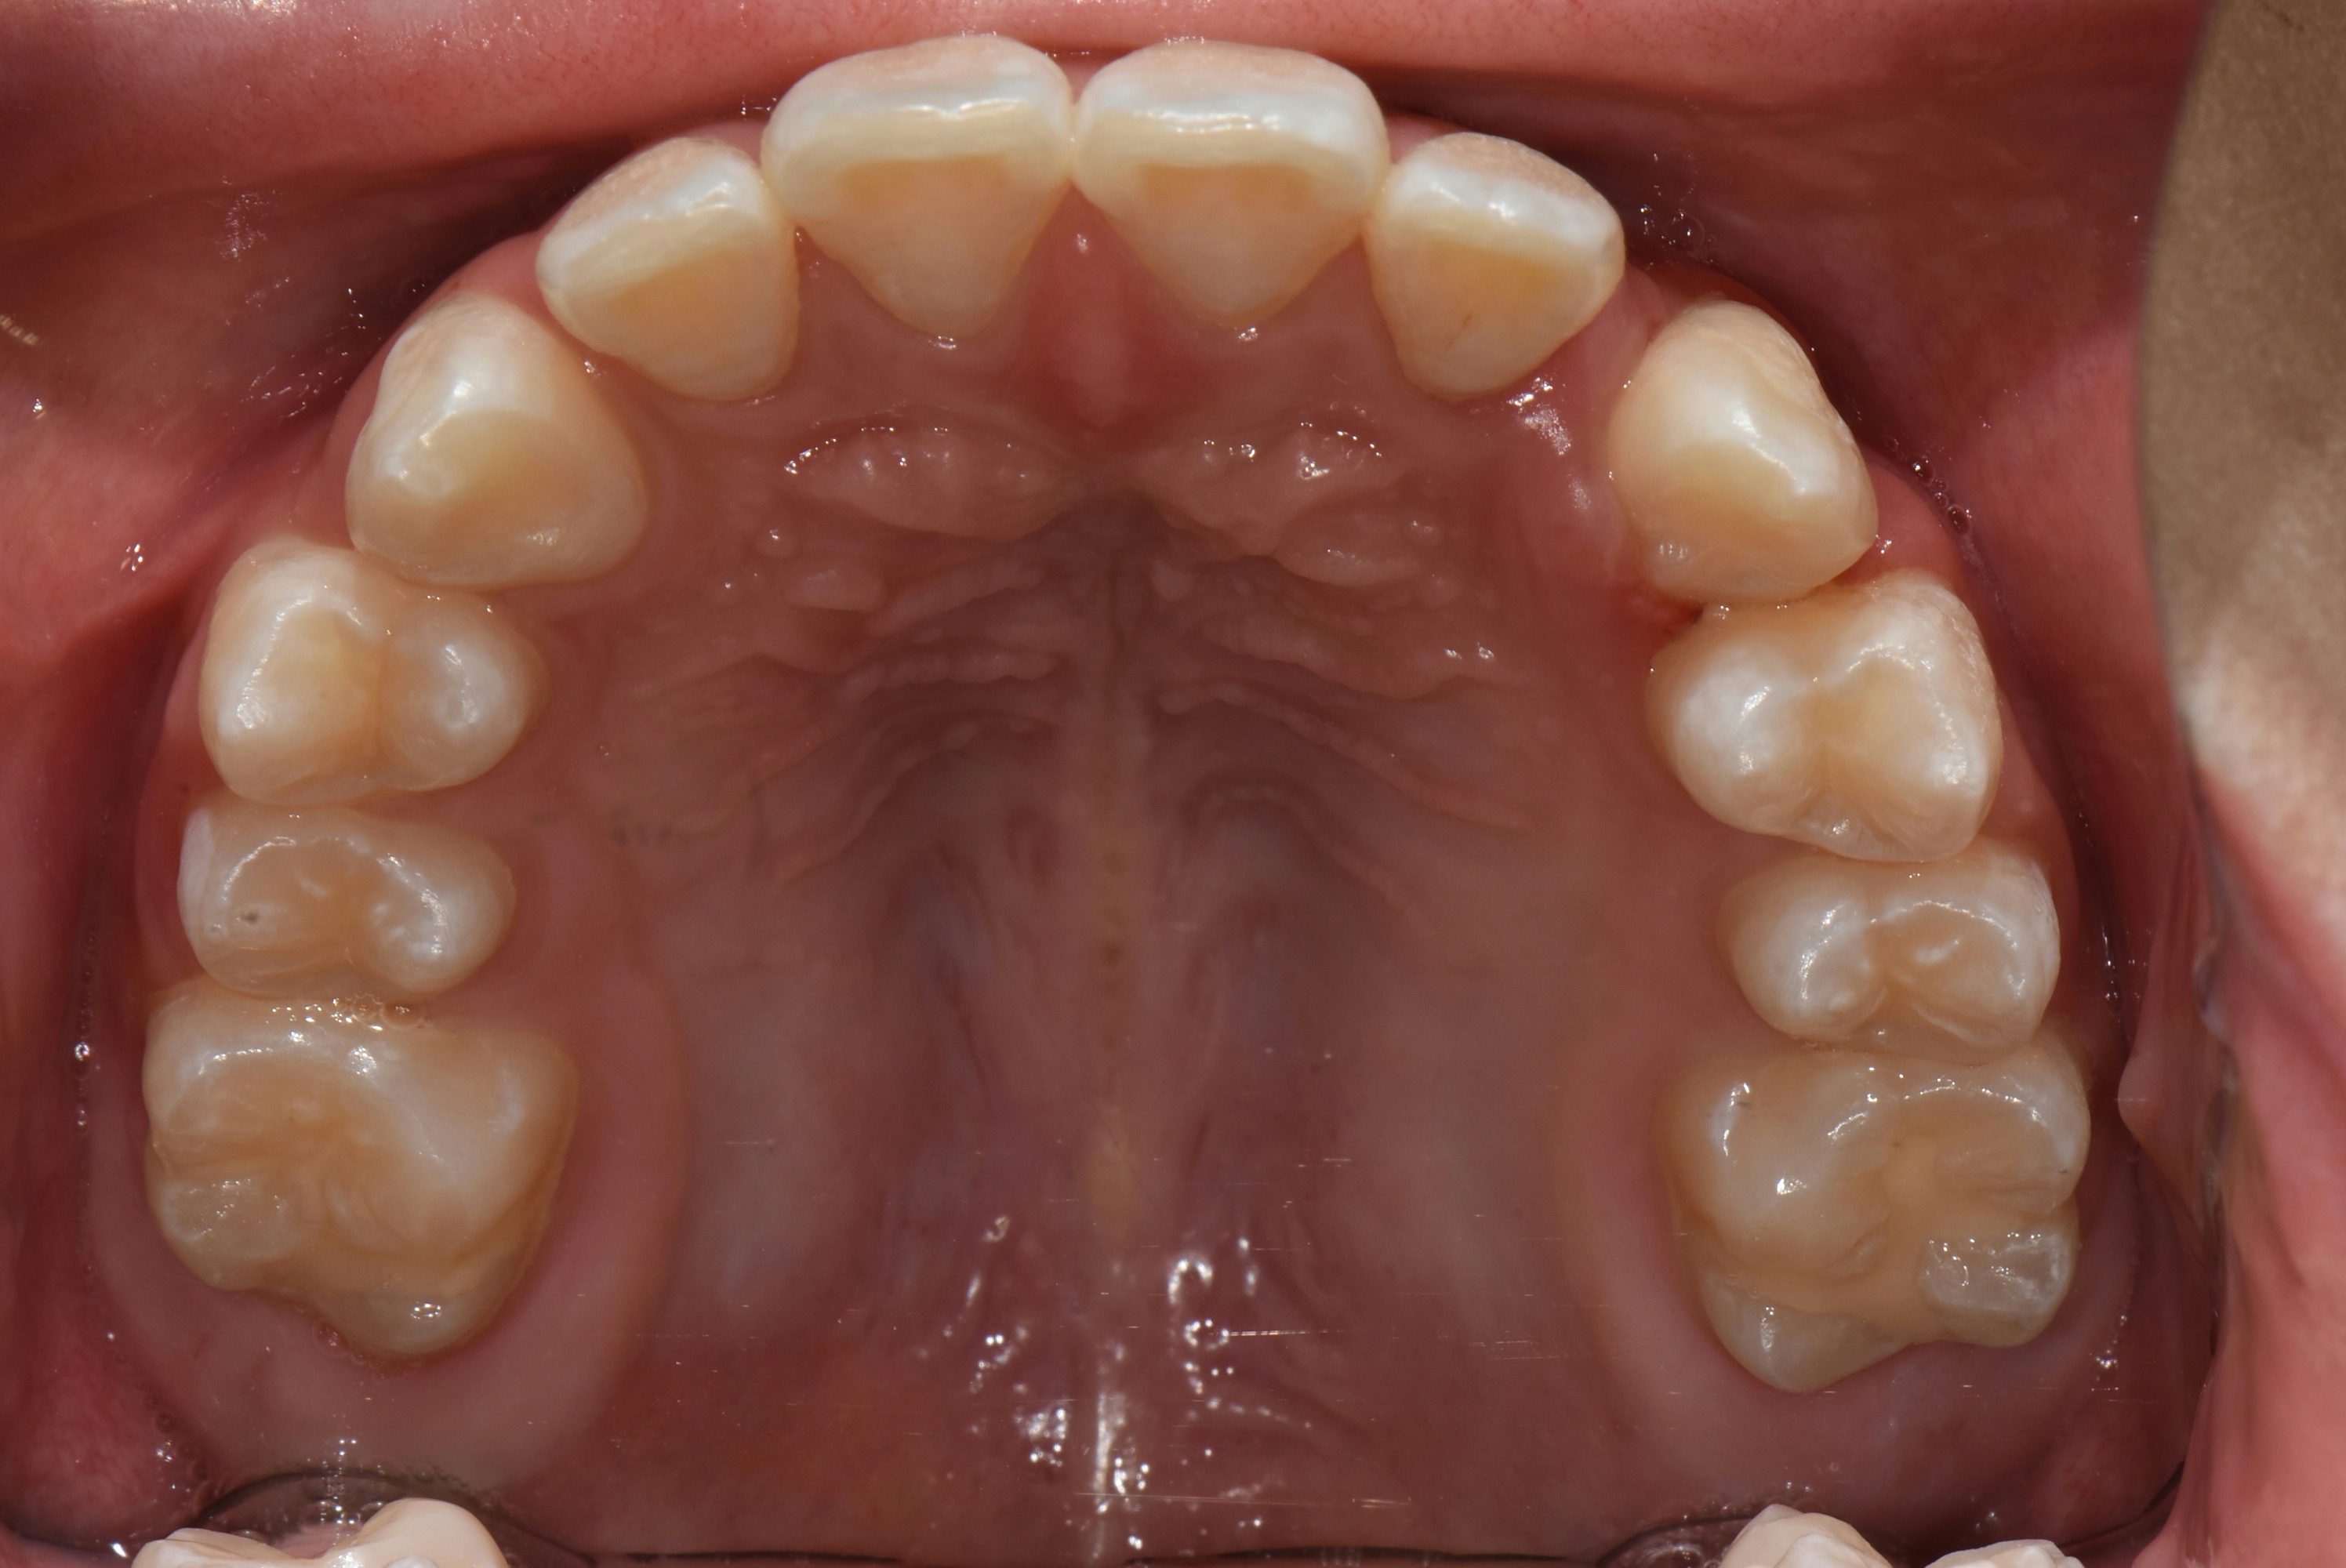

치료 후 사진입니다.